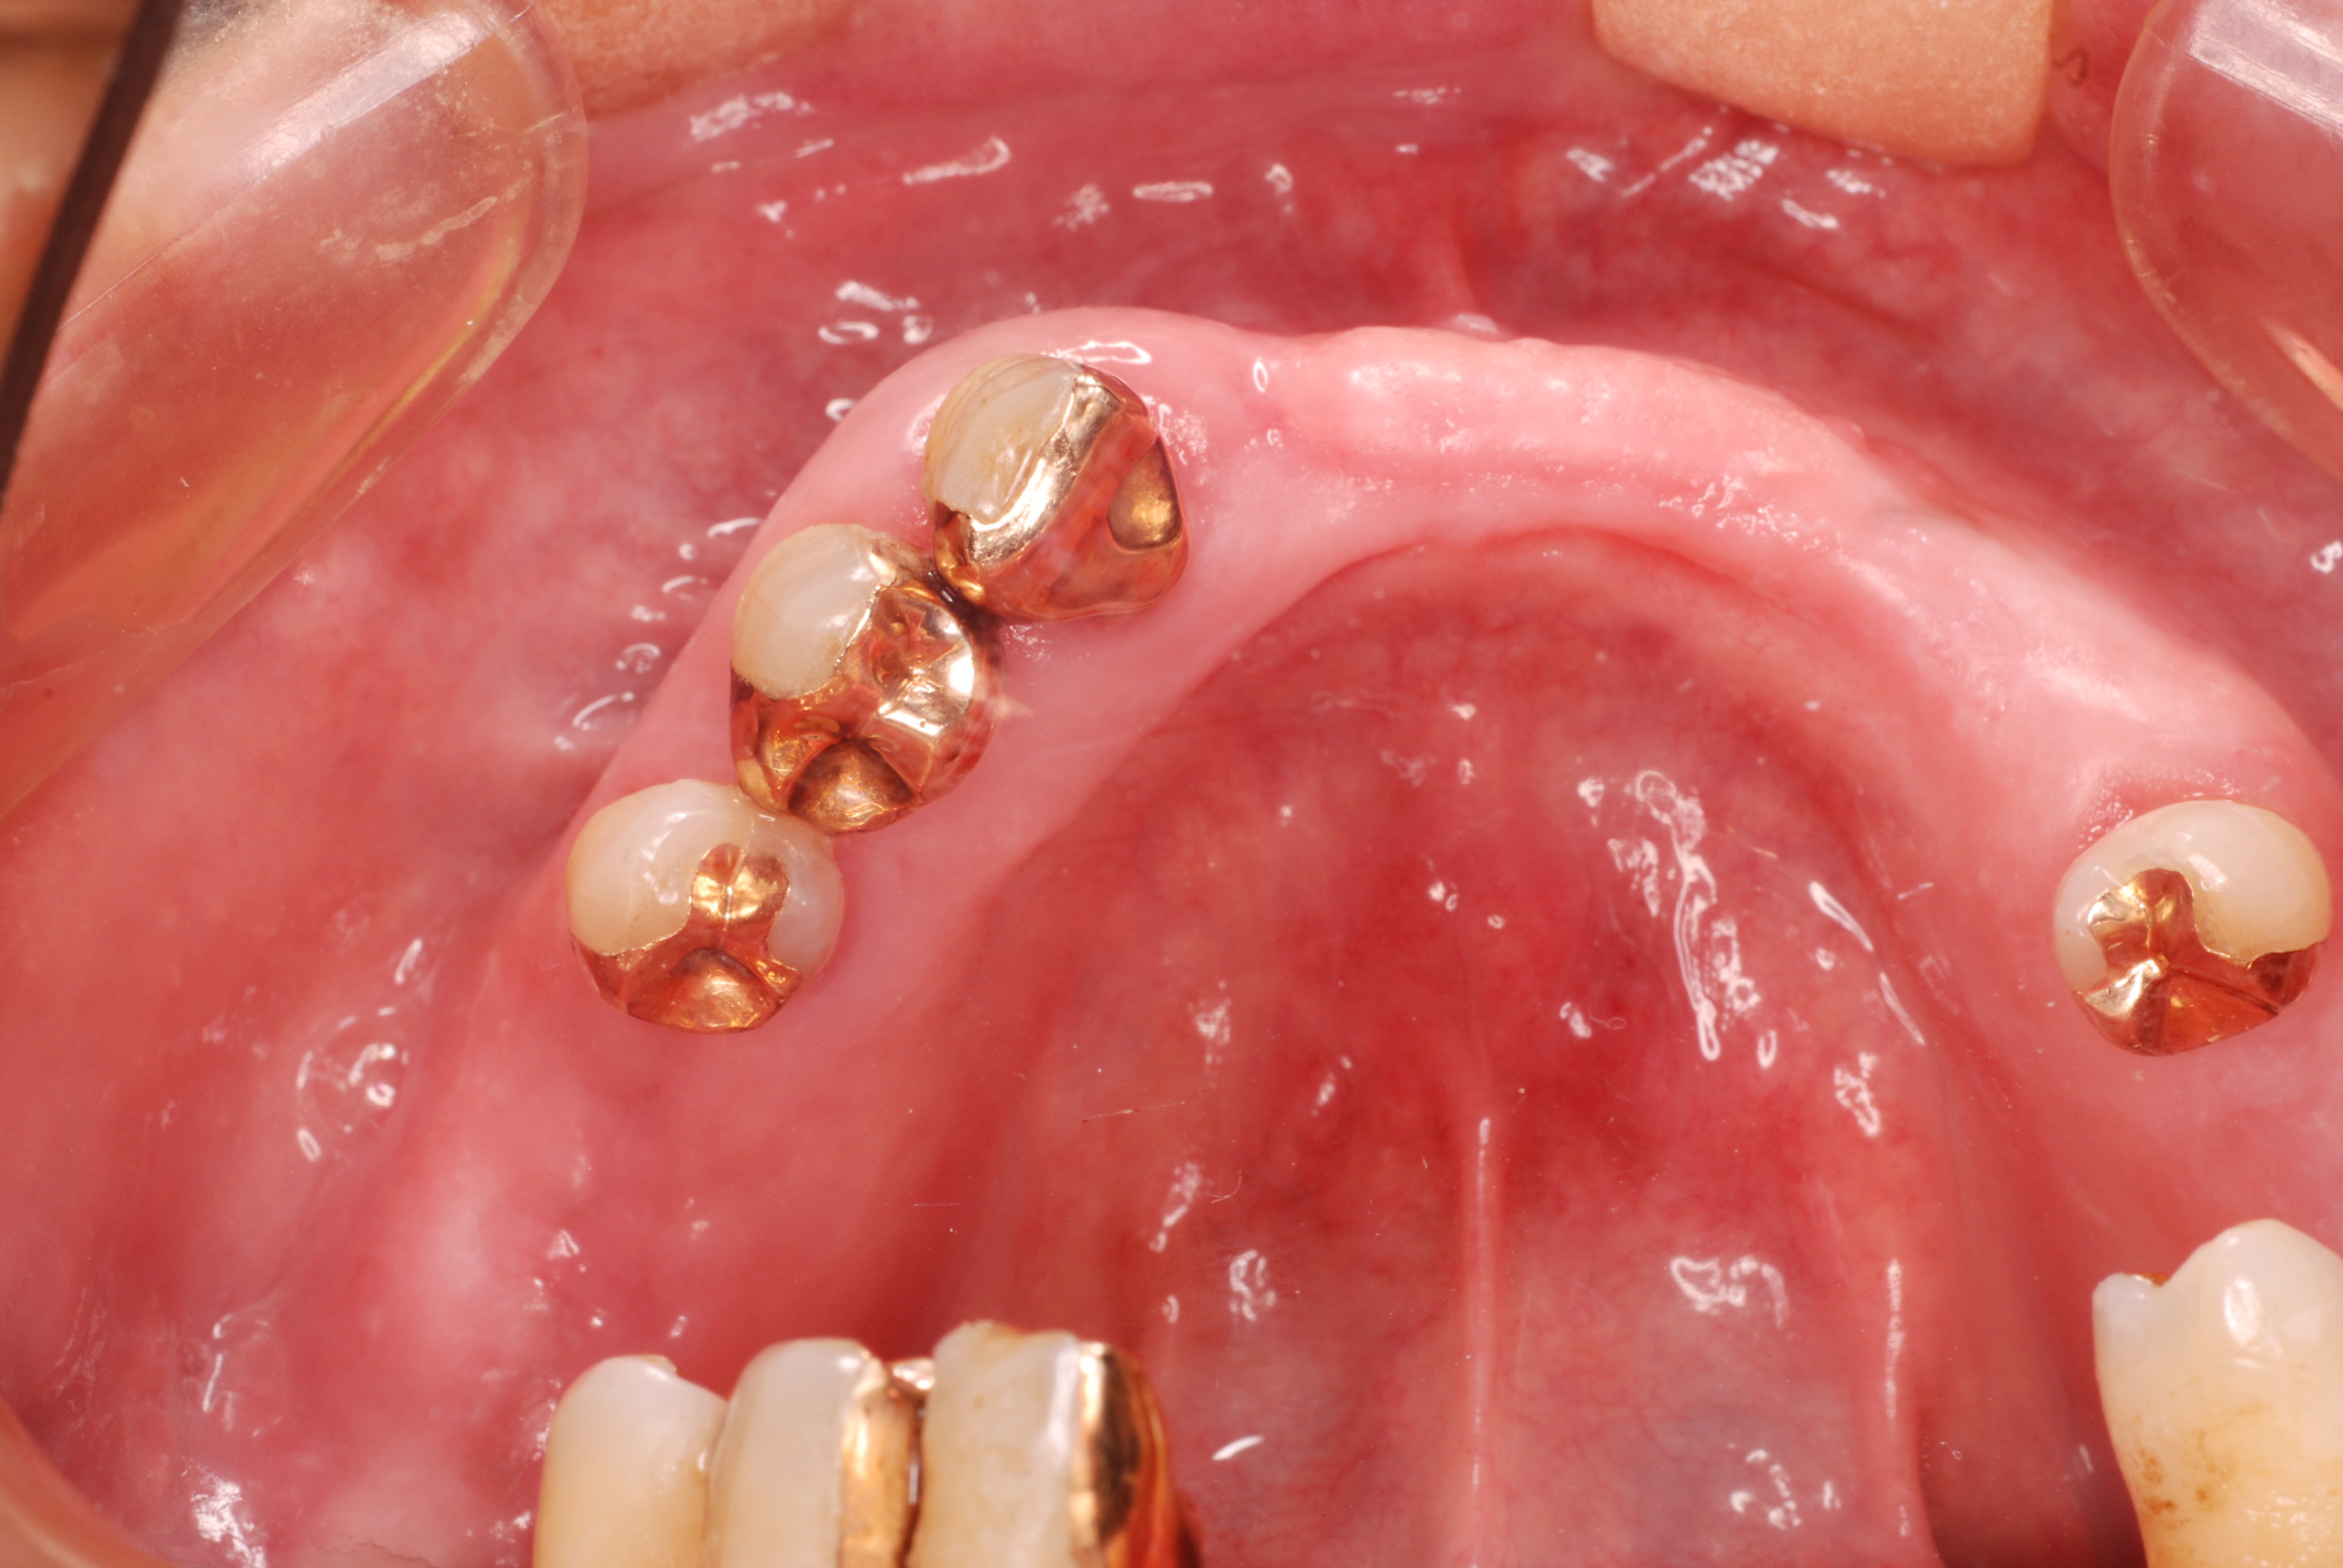

現実を見ればお口の中には“異物”である金歯、銀歯、セラミック、インプラントのオンパレードです。

これ等のものは、異物です。無い方が病気にならず健康でいられるのです。

必ずばい菌が侵入しないようにしてばい菌である虫歯を除去します。

銀歯の下はばい菌だらけです。こういうのはよくあります。取り残しですね。![treatment_05[1]](https://livedoor.blogimg.jp/netdental/imgs/3/a/3ad019d0-s.jpg)